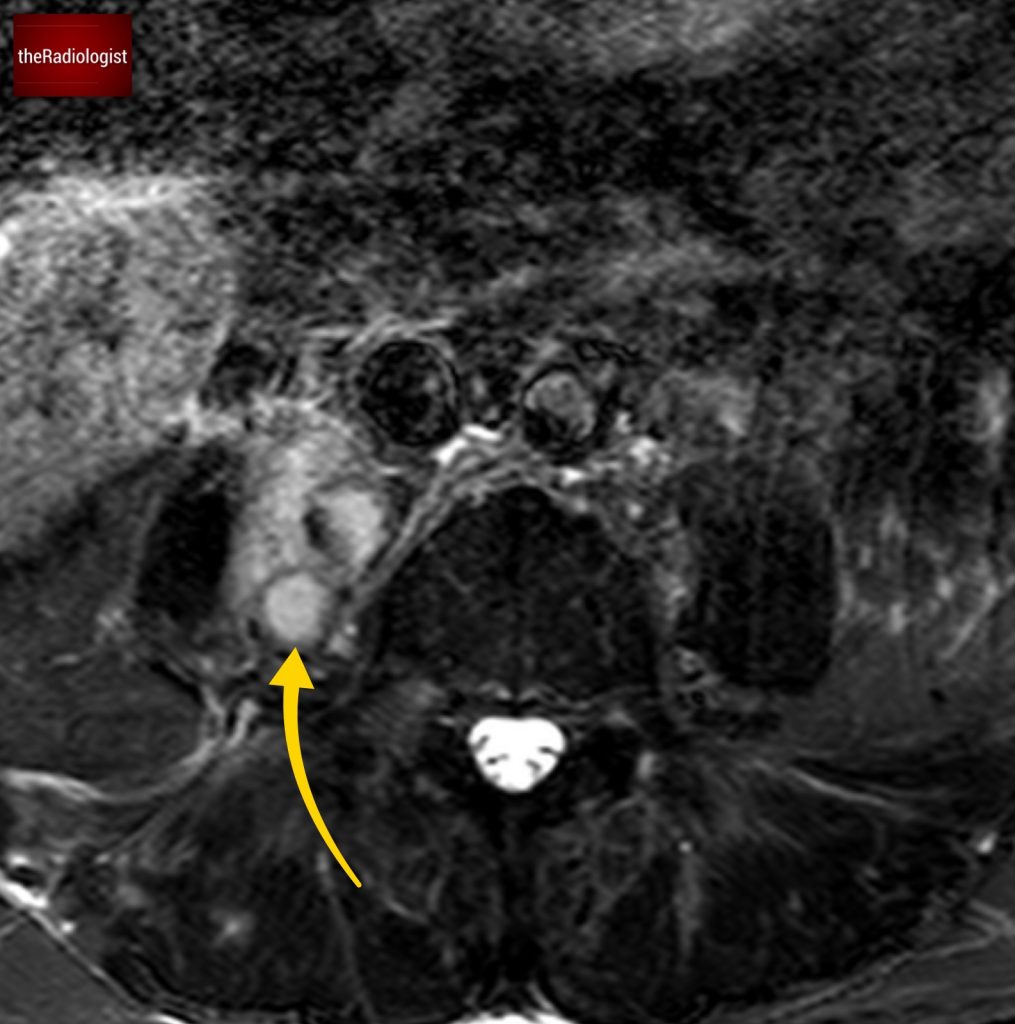

Due to pain the patient could only tolerate a few STIR sequences so we don’t have a complete scan but have a look at this axial STIR sequence below. We have high STIR signal within the right psoas with locules suggesting abscess formation.

Have a look at this axial STIR image from the MRI scan. Here we have high SITR signal within the right psoas with locules suggesting abscess formation.